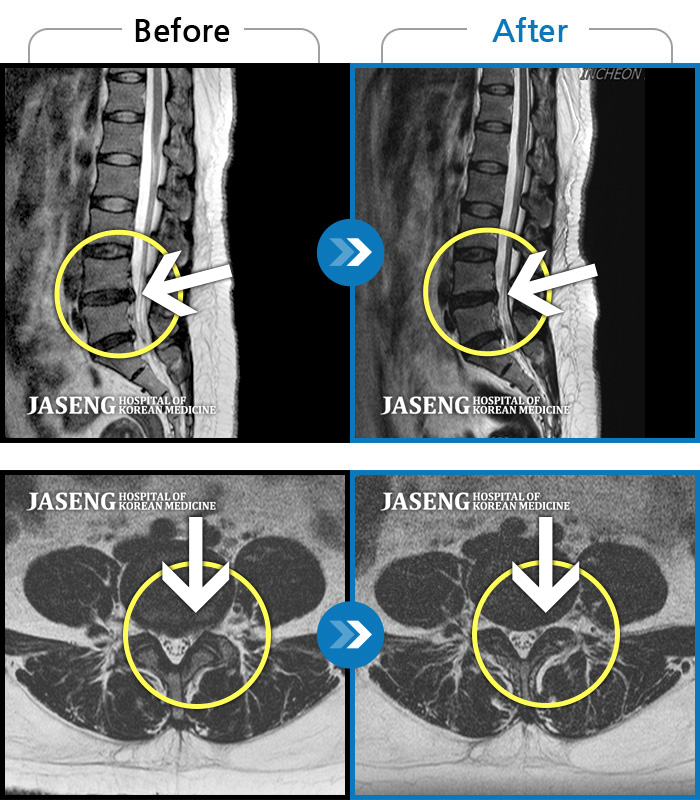

Before

After

환자에게 사전 동의를 받아 동일 조건에서 촬영되었습니다.

개인에 따라 치료 후 부작용이 발생할 수 있으니 의료진과 상담 후 치료를 진행하시기 바랍니다.

허리, 다리의 극심한 통증으로 거동이 힘들고 일상생활과 정상적인 업무가 불가능한 상태에서 내원하신 환자분입니다.

하지 저림과 통증이 개선되어서 일상생활이 너무 즐겁습니다.